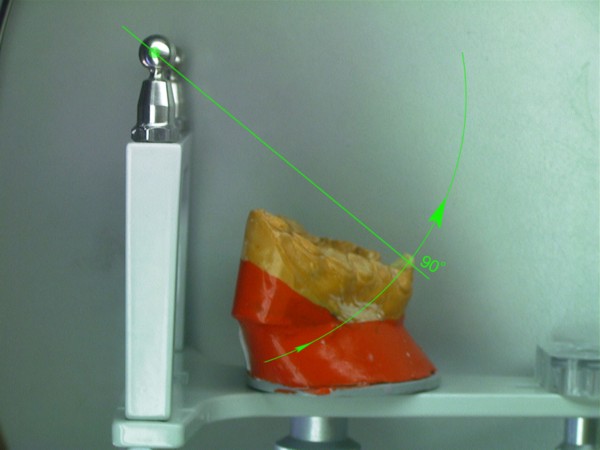

RESUMEN Es un desafío complejo conseguir una secuencia lógica de trabajo en la reconstrucción para una rehabilitación. SUMARY: Trying to acquire a logic working sequence in oral rehabilitation always becomes a defying challenge. The order of the different elements that deal with the whole dental system, as well as its positioning in each one of its planes, turn out into a series of rather difficult details that must be taken into consideration if we really aim towards satisfying results. Alineación Tridimensional- Macrotrípode de la Oclusión- Guía anterior- Microplanos. KEY WORDS: DESARROLLO: Las bases de todo el proceso tienen sus orígenes en una fuente de información tan fidedigna como es el concepto de la ALINEACIÓN TRIDIMENSIONAL La alineación dentaria en relación a unos parámetros regidos por la ATM y la guía anterior constituyen el MACRO TRÍPODE DE LA OCLUSIÓN creando una permanente dependencia de todo el sistema dentario con este; durante el cierre mandibular (la centricidad dentaria) así como durante los movimientos excéntricos (lateralidades y todas sus variantes intermedias). Dependencia que se vera incluso reflejada en detalles tan poco vistosos como son algunos factores elementales de la oclusión: la dirección de surcos. Así pues para sintetizar la totalidad del proceso de una forma breve pero clara destacaremos a continuación los conceptos fundamentales que se tuvieron en cuenta a lo largo de este trabajo. Dado lo extenso del tema nos centraremos fundamentalmente en: A- El desarrollo de La GUIA ANTERIOR, ya que consideramos que da origen al resto del proceso, B- Los VÍNCULOS DIRECTOS entre esta y los sectores posteriores. De la misma manera se muestran casos de estudio de pacientes semejantes al tratado, en que por cuestiones docentes se ha recurrido al encerado de estudio progresivo con ceras de diferente color a fin destacar donde empieza el desarrollo de cúspides, el origen de las crestas internas, así como los rebordes y el alineamiento a que están sujetos cada uno de estos elementos dentro de la individualidad cada pieza. A-GUIA ANTERIOR: Arco Esqueletal, Formas de Empotramiento, Alineamiento. Aunque en ocasiones pueda parecer que se forman situaciones por generación espontánea dada la escasez de información, siempre existen pequeños datos que nos proporcionan claves de referencia para empezar una reconstrucción. La que nos ayuda de una forma destacada y que no necesita de un vínculo directo con los dientes adyacentes, es la relación que se establece entre las piezas 31 y 41 y el movimiento de rotación del conjunto mandibular durante el cierre. Visto desde Sagital, si trazamos una línea entre la base de la emergencia de los centrales y la cabeza de cóndilo del articulador y a continuación proyectamos a 90º una segunda línea, hallamos la equivalencia al eje axial de la pieza (no así la altura). Este detalle nos puede suponer una gran diferencia en casos en los que el capital oclusal esta severamente dañado, allá donde no tenemos referencias anatómicas contiguas a la pieza que reconstruimos( fig 1). A partir de ello podemos empezar a considerar las proporciones en el eje vertical de la pieza ya bien sea a través de información remanente de los cíngulos linguales y de su tamaño en relación al resto del diente, o en ausencia total del capital oclusal (como es el presente caso) en base a las proporciones vestíbulo-linguales proyectadas a lo largo del eje vertical de la pieza. Las proporciones de centrales y caninos inferiores desde un plano horizontal reparten cada una de las caras libres en igual medida desde su borde incisal (50% Vestibular-50% Lingual), de manera que si proyectamos el borde de la primera pieza que hemos construido a partir del arco esqueletal , hacia la superficie que el lateral y canino ocupan en su emergencia (o siguiendo los rebordes/ alveolo en su defecto) podremos situar de una forma precisa el ecuador máximo de cada diente en sus caras libres, alineando así su conjunto (fig. 2). De la misma manera disponemos de unas proporciones entre el ancho V-L de la terminación amelo dentinaria de la pieza y el largo coronario (ej. El largo del canino inferior es aproximadamente eldiámetro V-L + un 30%). Dicha medida la prolongamos por el eje axial de la pieza para obte A partir de éste punto empezamos a pensar en la situación de las piezas superiores. La Dimensión Vertical, Centralizará la Mandíbula y nos aportará la El propio acoplamiento de los caninos de por sí implican una cantidad de desoclusión de las piezas (componente vertical), así como una calidad de desoclusión (componente horizontal del desplazamiento mandibular). Cabe destacar que para asegurar el buen funcionamiento de una guía anterior siempre es más favorable un punto de acoplamiento alto (desde un plano sagital seria una inserción notable del borde incisal inferior contra la vertiente palatina del superior, permitiendo así un importante recorrido en la desoclusión), así como una componente del canino superior muy verticalizada, lo cual impide que el maxilar inferior padezca un movimiento excentrico muy pronunciado, otorgando un patrón de movimientos mucho más verticales con menor distancia recorrida hasta el borde a borde entre caninos (evitaremos caer, eso si, en unos ejes de piezas convergentes -Clases 2/II-, situaciones con un alto grado de contención.) Asi pues prolongamos el eje del canino a partir de su perfil de emergencia. Respetamos las proporciones vestíbulo-linguales en 1/3 a 2/3 (fig. 3-4-5) y lo modelamos en vertical hasta una altura un 25 % mayor que su diámetro V-L a nivel cervical. Ello nos definirá un acople que una vez realizado en ambos caninos tendrá cuantificados unos valores de suma importancia que arrastrarán consigo todo el peso de la centricidad mandibular durante el cierre, así como la dimensión vertical o las propiedades desoclusivas, pues podremos observar como al realizar la lateralidad ya obtenemos espacios de separación uniforme en los cuadrantes posteriores allá donde todavía no hay piezas. Lo mismo hacemos con los centrales: proyectar canal radicular (en el encerado) si lo hay, respetar el ancho de cada una de las caras libres visto siempre desde un plano horizontal a la pieza, y proyectamos en vertical el diámetro cervical + 40-45% para terminar el largo de la pieza. Es importante no confundir la exposición de las caras vestibular y lingual de los dientes observándolos desde un plano horizontal como pieza individual, frente al mismo hecho visto desde su posicionamiento en el modelo, donde las piezas anteriores no se encuentran perpendiculares, sino ligeramente inclinadas hacia vestibular en su borde incisal, con lo cual sus vertientes palatinas se ven más expuestas. En esta fase ya tendremos un acoplamiento a partir del cual visualizar la Protrusiva y los movimientos intermedios compartidos con los caninos durante la función compartida de la guía anterior (fig. 6). Es lógico pensar que cualquier individuo que ha pasado por un proceso tan destructivo como este habrá sufrido movilizaciones a lo largo del tiempo y por lo tanto todas estas aportaciones teóricas son aplicables en la medida en que estemos dispuestos a hacer pequeñas variaciones tan solo milimétricas durante este proceso de alineado. En general cabe hacerse a la idea de que si bien los valores anatómicos / proporciones son prácticamente absolutos, no son igualmente cuantificables los movimientos o alteraciones a que ha sido sujeto un individuo que llega a este nivel de tratamiento (incluidos variaciones en exposición de reborde/alveolo por reabsorción), si bién es cierto que las leyes de proporciones dentarias y alineamiento conjuntamente tratadas pueden llevarnos a recuperar un orden desaparecido en una boca enferma. B-Elementos Intermedios: Escalones Negativos, Áreas de Transición y Microplanos. es mejor alinear el inferior y con ello se podrá acoplar todo el superior sobre él (resulta un tanto más complicado alinear bases de crestas triangulares y rebordes superiores antes que puntas de cúspide inferiores) (fig 7). Esta vendría a ser una referencia inmediata, pero hay que considerar otras. Entre ellas resaltar que según los biotípos se encuentran escalones o saltos negativos en el punto de transición entre anteriores y posteriores. Estos cambios de nivel van directamente asociados al potencial desoclusivo que genera la guía anterior frente al resto de piezas y son elementos funcionales que deben respetarse si se desea preservar la absoluta funcionalidad del conjunto. Este exceso anatómico marca una importante diferencia ya que su inserción en la cara antagónica de los caninos superiores es lo que proporciona la condición a la oclusión de mutuamente protegida. Dependiendo de los biotipos estos escalones pueden ser mayores o menores (fig 8). Al igual que los escalones, van apareciendo según avanzamos hacia los cuadrantes posteriores áreas de transición que suponen una proyección del desarrollo de los cíngulos, con el consecuente aumento del área cortical de las piezas, hasta el desarrollo de cúspides. Detrás de ello encontramos todo un compendio de proporciones que se respetan por igual en todas las denticiones que estudiamos, tanto en lo que respecta al ancho oclusal de cada elemento con las proporciones desde cada una de las caras libres (60% cusp de trabajo-40% cusp de corte) hasta las proporciones de la cara interna o el propio alineamiento de las bases de las crestas internas de las cúspides (fig 9). Normas que como se puede apreciar se han considerado incluso para prever las formas de piezas tan elementales como son las espigas y pernos asi como de la estructura de metal empleados en este caso gracias al encerado La información que aportamos en las fases iniciales siempre se puede alterar y modificar en este proceso de búsqueda de datos. Un proceso en el que sin duda el conocimiento anatómico, los biotipos y sus relaciones entre ejes, así como las relaciones craneométricas que desembocarán en el alineamiento de curvas, nos va a llevar a recopilar infinidad de datos vinculados entre si que permitan de una forma segura, enfocar con precisión un trabajo de estas características. «Tal como se aclara en la segunda entrega, la simbiosis entre clínico y técnico es prioritaria para obtener los logros fundamentales de una OCLUSIÓN ORGÁNICA. Si cuatro son las manos ejecutoras de una rehabilitación como la presentada,debo hacer hincapié en la excelencia de la labor clínica ejecutada por el Dr.Carlos A. Acuña Priano, en la preparación de muñones con alta precisión donde la lectura de los límites fué más que objetiva, como asi la concepción toda de un caso de alta complejidad no solo en el aspecto estructural y médico, sino también en el manejo de una personalidad dificil y controvertida de un paciente extremadamente destruido. El Dr.Carlos A.Acuña Priano,Odontólogo,Master en Implantología y Rehabilitación Oral,de amplia formación en temas de Oclusión, ha enriquecido mi labor de laboratorio como ya lo hiciera nuestro común maestro, el Profesor Anibal Alonso. A ambos, muchas gracias. Pedro Colomina Cursante de estudios de prótesis dental en la escuela Ramon y Cajal de Barcelona (1988)